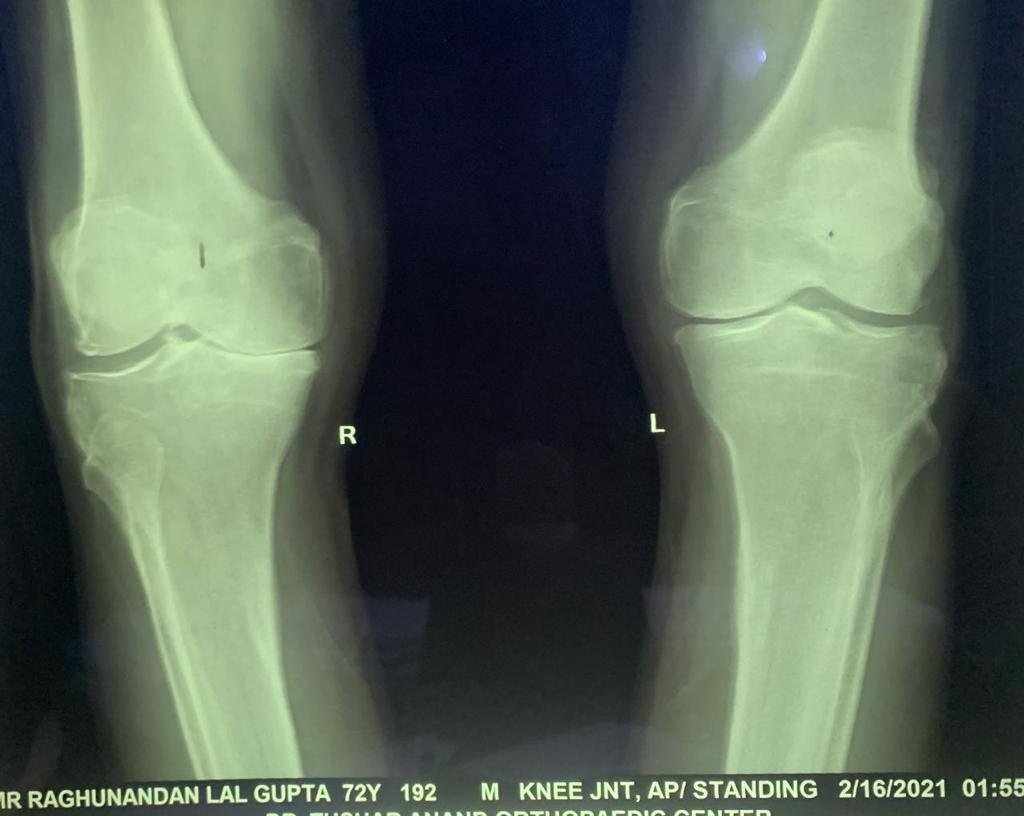

Total Knee Replacement

Name: RL Bansal

Date of Operation: 16 Feb 2021

Age: 72 Years

Before Surgery